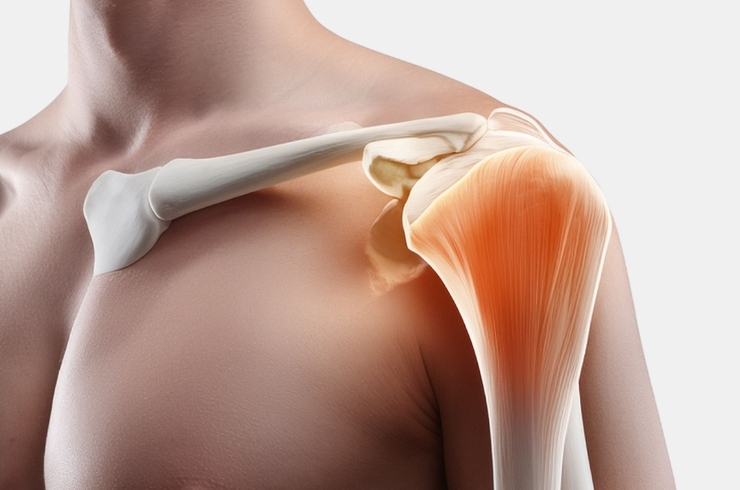

Comprehensive diagnosis and treatment for shoulder conditions, relieving pain, restoring mobility, improving strength, and ensuring long-term joint function and stability.

Advanced shoulder procedures to repair rotator cuff injuries, relieving pain and restoring strength and mobility.

Comprehensive care addressing shoulder stiffness, instability, and sports injuries, restoring mobility, strength, and pain-free function.

Persistent shoulder pain at night affecting sleep, often caused by inflammation, stiffness, or injury, requiring proper evaluation and targeted treatment.

Specialized shoulder replacement procedures relieving pain, restoring function, improving mobility in complex conditions.